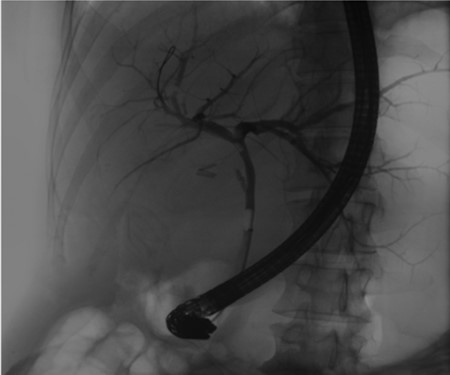

Follow-up ERCP 4 weeks later displaying resolution of all abnormalities.

A 35-year-old female with a medical history significant for acute biliary pancreatitis status post laparoscopic cholecystectomy, presented to the surgery clinic as a new consult for a large cystic liver mass with increasing abdominal pain for 2 weeks. Patient reported suffering from severe pain in right chest, shoulder and diffuse abdominally that worsened with standing. Patient complained of inability to inspire due to pain and a 10-pound weight gain over 2 months. She confirmed decreased appetite especially with solids, nausea and emesis, alternating constipation and diarrhea, bruising, and pruritus at night. Computed tomography (CT) scan demonstrated a peripherally septated 10 x 7 cm cystic mass in the liver with intrahepatic biliary dilation (Fig. 1). The patient was referred for endoscopic retrograde cholangiopancreatography (ERCP) to establish preoperative biliary anatomy and was found to have moderate compression of the common hepatic duct managed with a right hepatic biliary endoprosthesis (Fig. 2); no obvious communication of the biliary tree with the cystic lesion was seen. Patient symptoms persisted despite optimizing with a protein-rich liquid diet; thus, the decision was made to proceed with the surgical plan for an open partial central hepatectomy. The patient was taken to the operative theater. After induction of general anesthetic, an upper midline incision was made. Inspection of the abdomen and liver showed no metastatic lesions grossly or with ultrasonographic imaging. The cyst was visible upon entry into the abdomen with no solid component to the mass in proximity to the cystic neoplasm. The second portion of the duodenum was adherent to the cyst with inflammatory adhesions and was quite boggy. A partial central hepatectomy was performed; a 3 mm biliary duct was found communicating to the cyst only with no drainage to the minimal liver parenchyma that was removed (Fig. 3). The cyst was resected en-bloc and was sent for permanent section (Fig. 4), which diagnosed the tumor as a low-grade mucinous cystic neoplasm measuring 8.5 × 7.2 × 6.4 cm. Microscopy revealed a smooth-walled, multiloculated cyst filled with a yellow-golden, semi-transparent and mucinous fluid (Fig. 5a–c). The cyst was lined by a mucinous epithelium with ovarian-type stroma. No high-grade dysplasia or malignancy was identified. The postoperative course was uneventful, and the patient was discharged on postoperative day 6. At the 4-week postoperative visit, the patient was healing well with some incisional soreness; patient was seen for removal of her biliary endoprosthesis, and ERCP found left sided intrahepatic duct biliary dilatation including a small biliary fistula from the left system (Fig. 6) with the appearance of torque on the extrahepatic biliary tree. A biliary endoprosthesis was left in place, and the patient returned for repeat ERCP 4 weeks later with resolution of all findings (Fig. 7). At present, patient remains alive with no signs of recurrence.